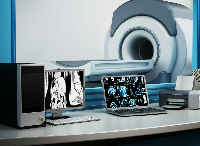

Мобильный рентгенаппарат + оцифровщик. Получение рентгеновского изображения на экране ноутбука. Вариант за 1,4 миллиона рублей под ключ.

Магнитно-резонансная томография (МРТ):один из самых эффективных методов диагностики заболеваний